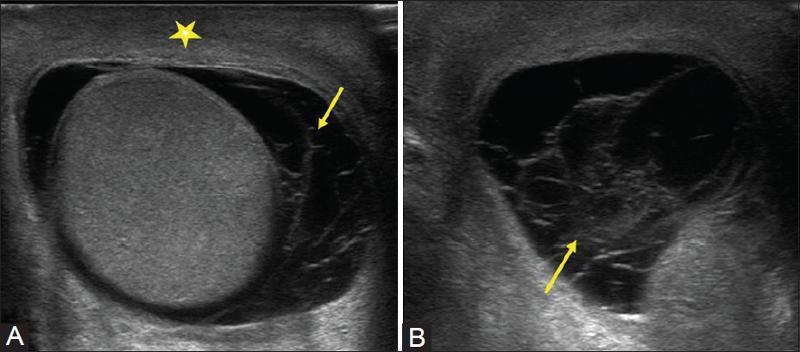

most common fluid collection of the testicle

Hydrocele

serious fluid between the tunica vaginalis

Varicocele

left side

most common correctible cause of male infertility

Varicocele